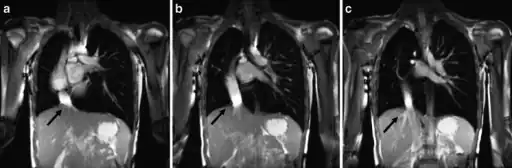

-

a-c) Scimitar syndrome in a young male- Breath-hold coronal 2-D steady-state free precession demonstrates the anomalous partial pulmonary venous return -

The diagnosis is made by transthoracic or transesophageal echocardiography and selective pulmonary angiography.[6] More recently by CT angiography or MR Angiography.